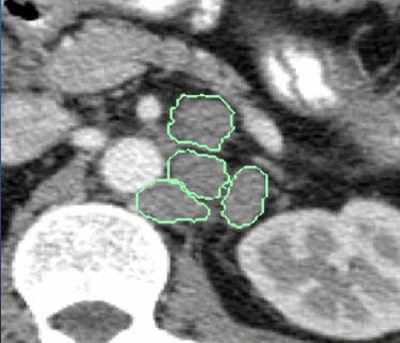

A radiologist manually examined each scan, segmenting the enlarged lymph nodes and sampling 2D views of voxels for each lymph node candidate in three planes. From these, the group extracted 15 x 15-pixel squares of the lymph node boundaries and used a technique called sketch tokens to extract shapes within these regions using k-means clustering with 150 representative lymph node contour classes.

The sketch tokens "look like little binary images showing the various types of shapes that occur on the boundaries of lymph nodes," Summers said.

Midlevel boundary cues look like nothing more than squiggly lines, Summers allowed, but they "eliminate lots of shapes that don't look like lymph nodes," he said. "There are a lot of other shapes in those parts of the body that are more linear than curved, and might have more jagged edges rather than smooth, so some of these things like smoothness and rate of curvature are what characterize lymph nodes. Things like bones, blood, and bowel get excluded."